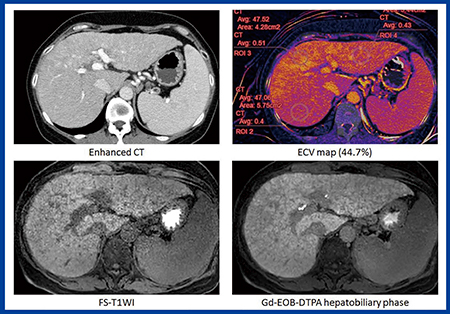

通常,正常肝のECV値は脾臓より低いが,症例1〔50歳,男性,原発性胆汁性肝硬変(F4)〕では脾臓よりも肝臓のECV値が高くなっている(図3)。ECV値は44.7%で,肝臓の線維化が非常に進行していることがわかる。

図3 症例1:50歳,男性,原発性胆汁性肝硬変(F4)